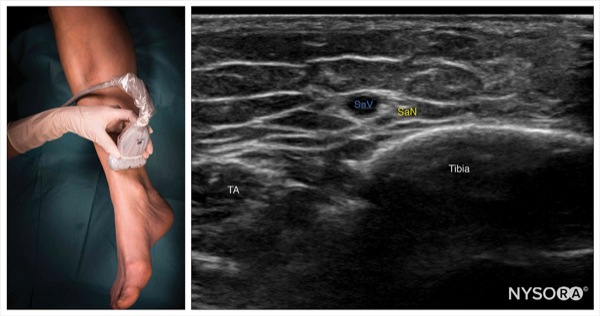

To Block the Saphenous Nerve

Place the transducer in a transverse orientation just proximal to the medial malleolus (Figure 9).

Identify the saphenous nerve as a small hyperechoic structure next to the great saphenous vein. The great saphenous vein is the main ultrasound landmark for this block because the nerve may not always be seen.

Insert the needle using an in-plane or out-of-plane approach toward the fascial plane surrounding the great saphenous vein (Figure 10).

Inject 1 to 2 mL of local anesthetic to confirm proper needle position by observing the spread surrounding the saphenous vein and nerve.

Complete the block with a volume of 3 to 5 mL.